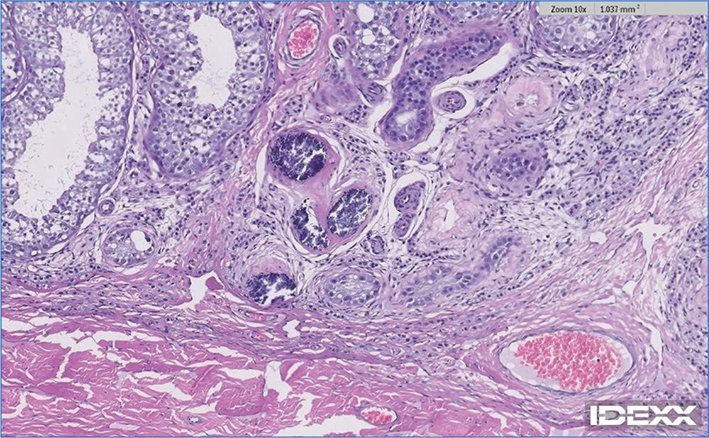

Case 2: A 3½ year, intact male Rottweiler with a history of prostate disease was presented for ultrasonographic evaluation in February of 2022. Testes were judged to be somewhat small and bilateral testicular microlithiasis was identified (Figures 5 and 6). Breeding soundness examination was performed in January of 2023. Abnormalities noted on general physical examination were mild dental disease and a grade III/VI cardiac murmur. Both testes were small, with an estimate of them being half the size expected for a dog of this breed and size. Semen was collected by manual ejaculation with no teaser female dog present but with exposure to estrous dog vaginal swabs. Libido was high; 4.5 ml of semen was collected and that was azoospermic. Semen alkaline phosphatase concentrations suggested incomplete ejaculation despite good libido and normal erection and reproductive behavior. Dog was castrated and testes were submitted for histopathology in April 2023. Both testes contained widely scattered foci (Figures 7 and 8; blue arrows) of intratubular mineralization (500 µm in maximal diameter with < 200 µm in diameter) without associated inflammation. Outside of these mineralized areas, there were rare small interstitial infiltrates of lymphocytes and plasma cells and rare individual atrophied seminiferous tubules.

Figure 7.

Figure 7. Testicular histopathology (low magnification) of Case 2

Figure 8.

Figure 8. Testicular histopathology (high magnification) of Case 2